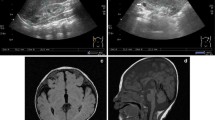

For standard karyotyping, routine cytogenetic analysis of GTG-banded metaphase chromosomes was performed on phytohaemagglutinin (PHA)-stimulated peripheral blood lymphocytes. Standard cytogenetic analysis of the proband showed a normal female karyotype (46, XX), which excluded numerical or large-scale structural chromosomal rearrangements as a cause of the complex phenotype. Besides, bidirectional target Sanger sequencing did not detect any pathogenic point mutations in intron 5 sequence of LMBR1 (ID 64327) as well as in protein-coding regions of NKX2.5 (ID1482) and TBX5 (ID6910) genes earlier reported to be associated with triphalangeal thumb, structural heart defects, or combined heart-hand pathology such as Holt-Oram syndrome, respectively.

To screen for copy number variants (CNVs), oligonucleotide array-based comparative genomic hybridization (array-CGH) was carried out. As a platform, Agilent 180 K array with median probe spacing 13 kb was used (SurePrint G3 Human CGH Microarray, Agilent Technologies, Santa Clara, CA, USA). The sample preparation and hybridization procedure were performed following the manufacturer’s recommendations. The data obtained were processed and analyzed using Feature extraction (v9.5) and CytoGenomics (v3.0.1.1) Softwares (Agilent Technologies). CNVs (gains and losses) were called using an aberration detection statistical algorithm ADM-2, with a sensitivity threshold of 6.0. Clinical significance of the findings was evaluated based on the data from publically available databases of normal and pathogenic genome variants, including Database of Genomic Variants (DGV), Online Mendelian Inheritance in Man database (OMIM), Database of Chromosomal Imbalance and Phenotype in Humans using Ensembl Resources (DECIPHER). Array-CGH revealed an interstitial microduplication spanning 299 kb region at 7q36.3 cytoband (arr[GRCh37] 7q36.3(156385810_156684811) × 3) that encompassed three annotated genes (C7orf13, RNF32 and LMBR1) (Fig. 3a, b). The gain of 7q36.3 region was confirmed by quantitative polymerase chain reaction (qPCR) using SYBR Green Master Mix (Evrogen, Russia) (Fig. 3c). The assay was performed for LMBR1 gene sequence (RefSeqGene NG_009240.2). The quantity assessment of the target sequence was carried out relative to a normal control DNA. The relative copy number was evaluated using the comparative ΔΔCt method with GAPDH and SHH genes being used for normalization. The qPCR primers were the following: F 5′-ATGCTTTGTGCGGGAAATCCA-3′, R 5′- GTCTCCTCCCTCCTGAATCCAT-3′ (LMBR1); F 5′- CTTAAAAAGTGCAGGGTCTGGC-3′, R 5′-TGCTGTAGCCAAATTCGTTGTC-3′ (GAPDH); F 5′- TGTTTGCTCTTCGGGCAGAT-3′, R 5′-CGTCTGTTACCGTCCTCACC-3′ (SHH). The samples were run in triplicate and the data were analyzed and illustrated in the GraphPad Prism software. The duplication was seen as a ~ 1.5 fold relative copy number. The CNV was submitted to the European Variation Archive (EMBL-EBI, https://www.ebi.ac.uk/eva/), accession PRJEB32845. The CGH and qPCR analysis of the probandʼs mother detected the same microduplication (the data not shown). No additional clinically-relevant copy number variants were identified in the proband and her mother. DNA samples from other relatives were not available for genetic analysis.

Detection of 7q36.3 duplication. a, b High-resolution cytogenomic analysis of the proband using comparative genomic hybridization on Agilent 180 K microarray. a The whole view of chromosome 7. The microduplication is shown by an arrow. b The enlarged 7q36.3 region with imported tracks of gene annotations. The data illustrate the presence of a ~ 300 kb microduplication (arr[GRCh37] 7q36.3(156385810_156684811) × 3) encompassing LMBR1, RNF32 and C7orf13. ZRS and MACS1 enhancers of SHH are depicted as coloured bars. c Confirmation of 7q36.3 duplication using quantitative real-time PCR analysis (qPCR). qPCR data revealed three copies of the LMBR1 gene in a patient DNA sample as compared to two copies of the gene in a control DNA sample. The data were normalized against GAPDH and SHH genes using the comparative ΔΔCt method